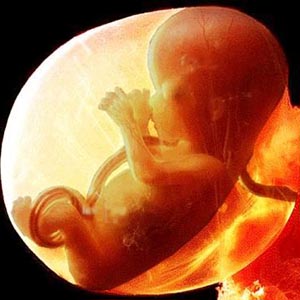

Całe dziecko ma teraz rozmiar wapna. Długość ciała wynosi 44-60 mm, a waga około 8 g.

rozmiar płodu w 11 tygodniu

Wszystkie narządy i układy dziecka są już uformowane. Są w innym stanie. Na przykład małe serce bije długo i całkowicie. Ale nie ma jeszcze szkieletu, tkanka kostna pozostaje w stadium chrzęstnym. Jak dotąd tylko czerwone krwinki (czerwone krwinki) są zawarte we krwi, a białe krwinki powstają później. Ale struny głosowe prawie się rozwinęły, chociaż dziecko nie będzie ich wkrótce potrzebować.

Tak wygląda płód w 11 tygodniu (klikalny):